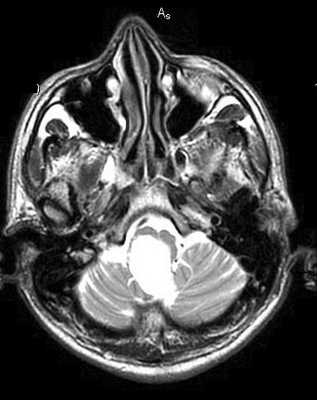

![эпенд 4-акс-Т2]()

МРТ головного мозга. Эпендимома IV желудочка. Сагиттальная Т1-зависимая МРТ, аксиальные Т2-зависимая МРТ и МРТ типа FLAIR.